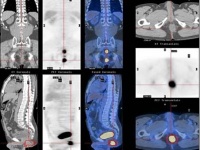

软组织肿瘤的病程是很不一致的,这与肿瘤的生长速度、出现的症状、病人的耐受性及其对肿瘤的认识和警惕性有关。一些可以迅速广泛地发生转移;而另一些则可能极少且晚期才转移。因此,病程与肿瘤的恶性程度并无必然的同步关系,也就是说病程长者不一定都是良性,病程短者也不一定都是恶性。反之亦然。几乎所有这一类肿瘤均表现有沿解剖位置,诸如神经、血管、肌束筋膜造成局部侵犯的倾向,因此肿瘤实际延及的范围常远大于体检所认为的范围。软组织肿瘤具有早期发生血行播散的特点,通常为肺转移,肝、骨、脑等其他器官的转移则少见,引流区淋巴结的转移不常发生,但在滑膜肉瘤和横纹肌肉瘤则可能。

恶性软组织肿瘤通常生长迅速、体积巨大,浸润和破坏周围正常组织。肿瘤本身可有坏死出血继发感染,并且经常有广泛的血行播散转移至肺、骨、皮下、脑、肾上腺胰腺等脏器。患者往往死于恶液质,严重出血及广泛转移;各种类型的恶性软组织肿瘤的恶性程度也有显著差别,根据其血行转移多少可粗略地分为三类:高度恶性的有圆型细胞脂肪肉瘤、多形性脂肪肉瘤、腺泡状横纹肌肉瘤、滑膜肉瘤、血管内皮肉瘤、淋巴管肉瘤等;中度恶性的有深部恶性巨细胞瘤、多形性横纹肌肉瘤、透明细胞肉瘤、平滑肌肉瘤等;低度恶性的有上皮样肉瘤、浅部恶性巨细胞瘤、纤维肉瘤、高分化的粘膜脂肪肉瘤等。